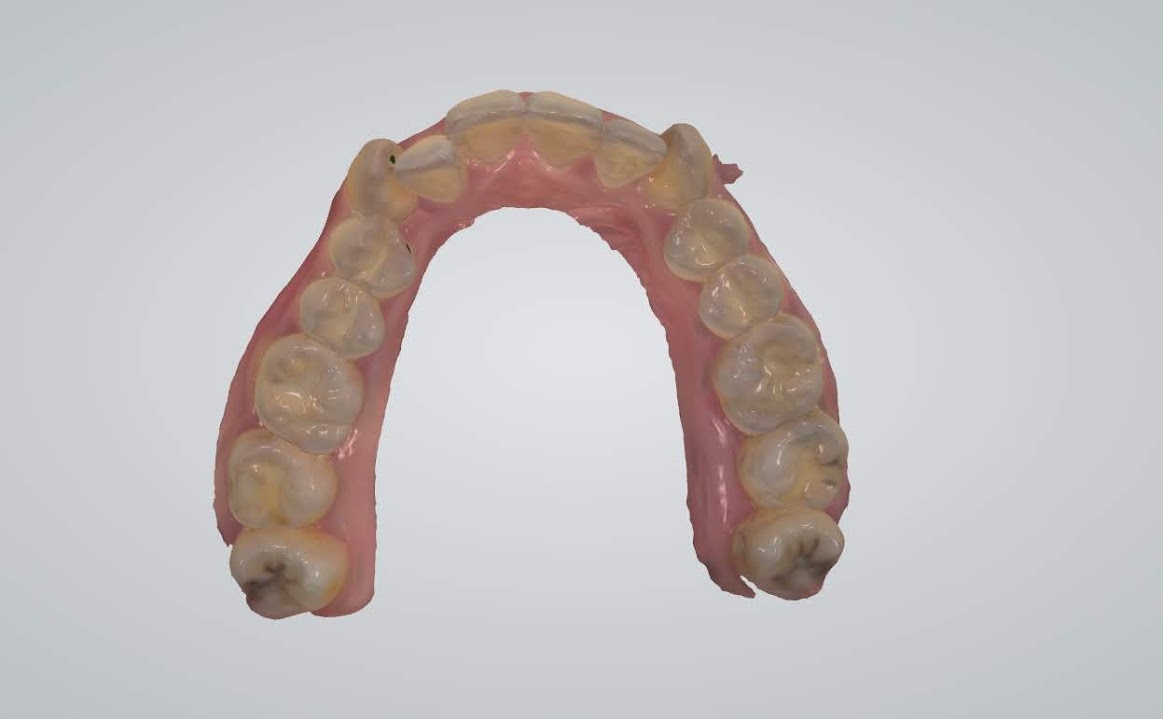

另外讓秤秤驚艷的先進設備還有這個-數位口腔掃描

能讓你清楚的看到每顆牙齒的長相、咬合狀況等,甚至連蛀牙、牙結石都照的很清楚,這樣當醫師在說明你的口腔狀況時,才能夠更了解且更快進入狀況

一直以來都覺得自己是滿口爛牙,再聽了醫生講解和看了自己的X光片、口腔掃描照後更加確定了~